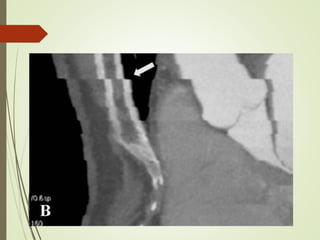

Normal LIMA to LAD graft (arrow)

Normal venous graft to OM

Normal LIMA toLAD graft (arrow) Normal venous graft to OM